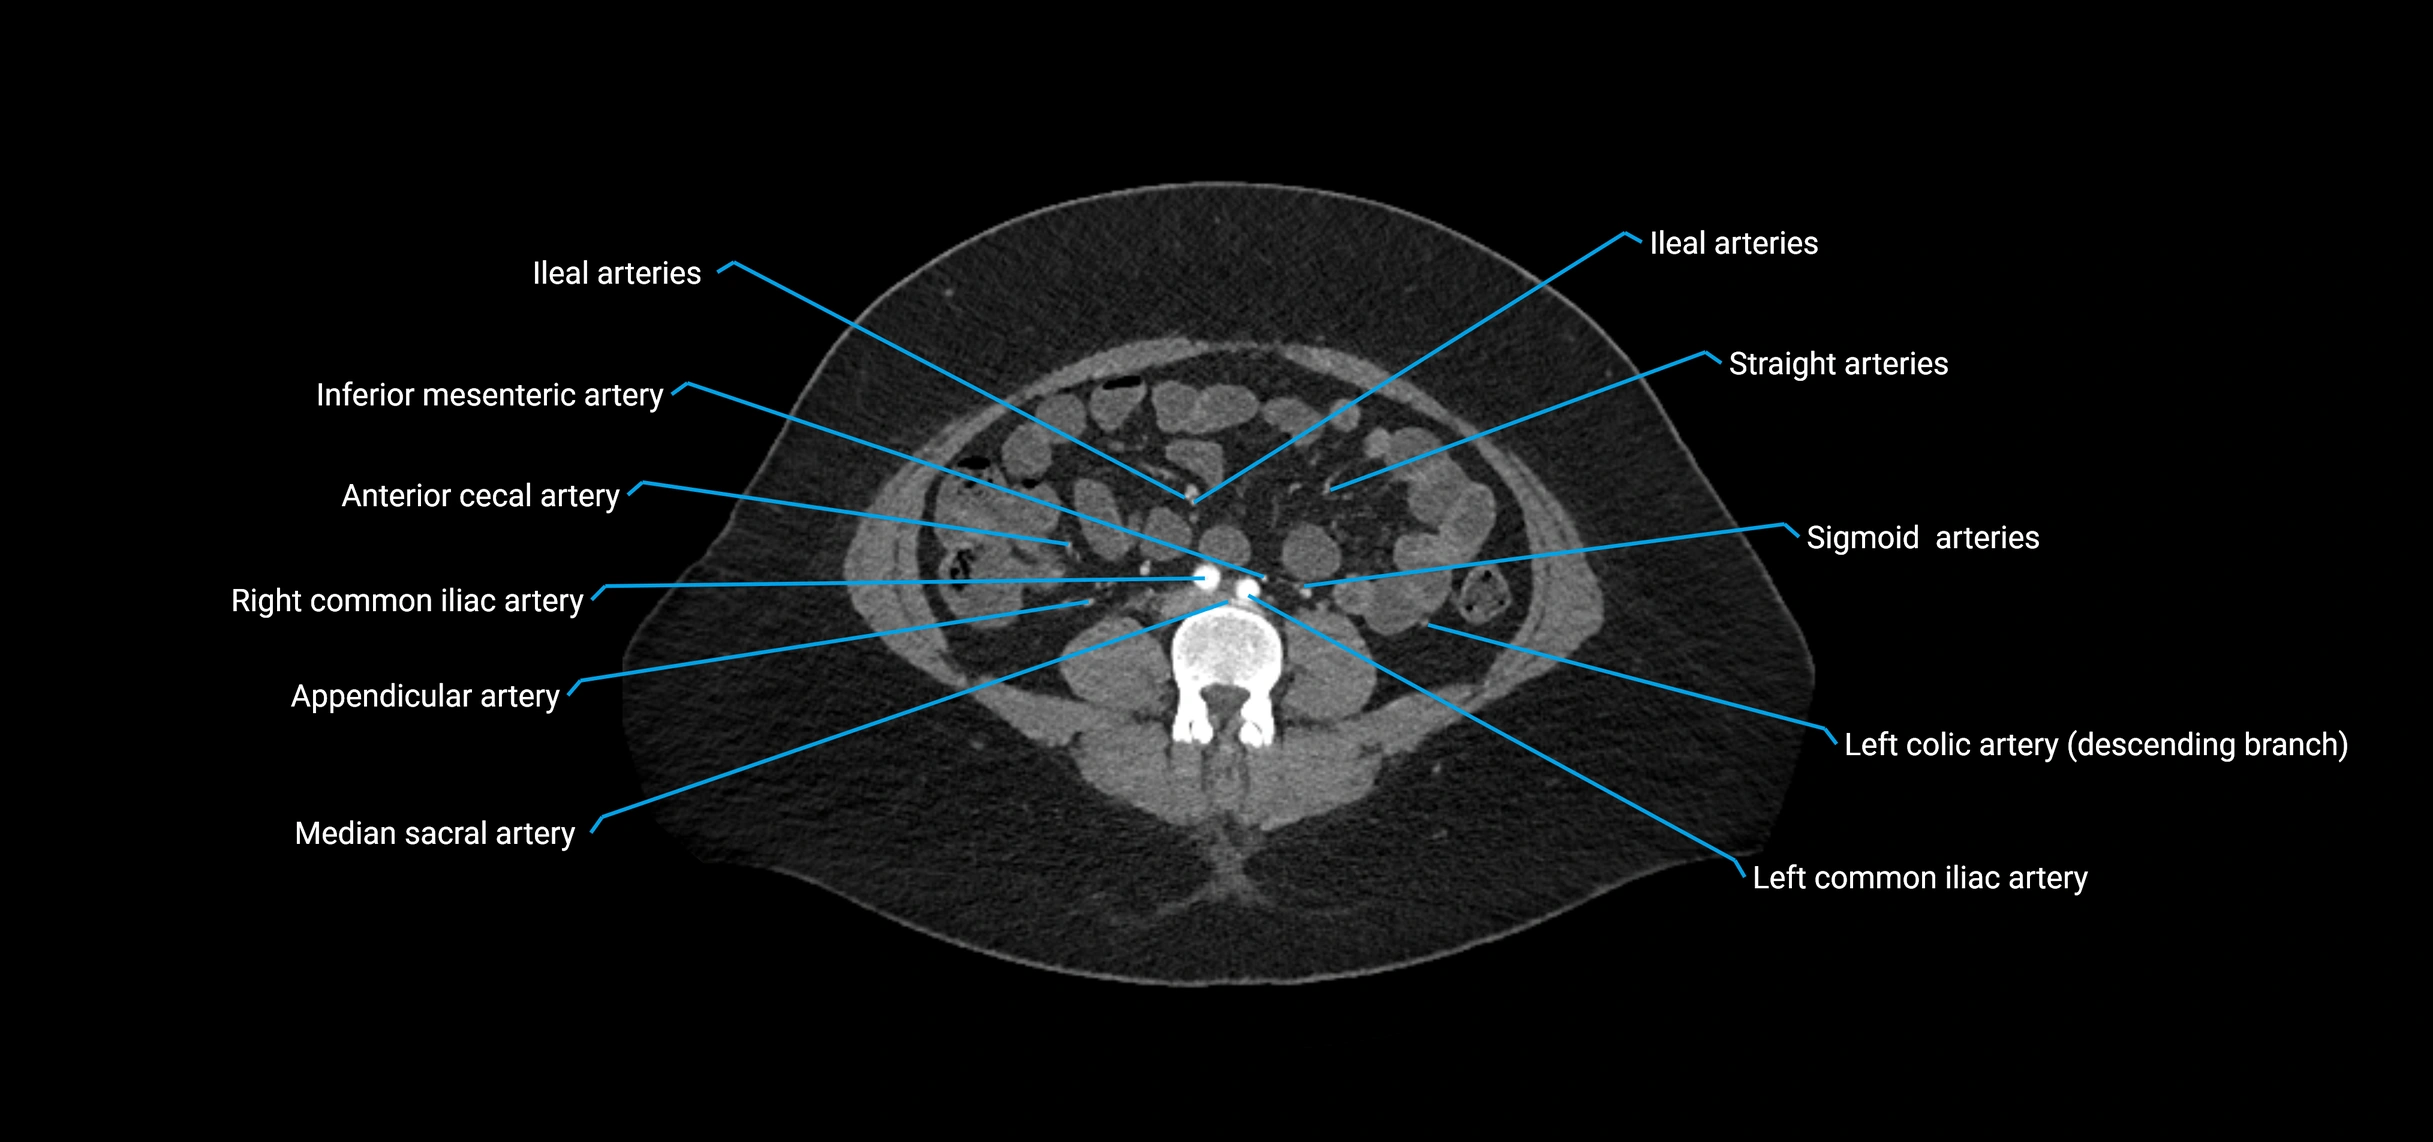

Branches

• Unpaired visceral branches: celiac trunk, superior mesenteric artery (SMA), inferior mesenteric artery (IMA)

• Paired visceral branches: middle suprarenal arteries, renal arteries, gonadal arteries (testicular or ovarian)

• Parietal branches: inferior phrenic arteries, lumbar arteries, median sacral artery

• Terminal branches: right and left common iliac arteries

CT Appearance

Contrast-enhanced CT (CTA):

• Gold standard for abdominal aortic imaging

• Provides excellent detail of lumen, wall, aneurysm, thrombus, and branch vessels

• Multiplanar and 3D reconstructions help in aneurysm measurement, stent graft planning, and dissection evaluation

CT images

image